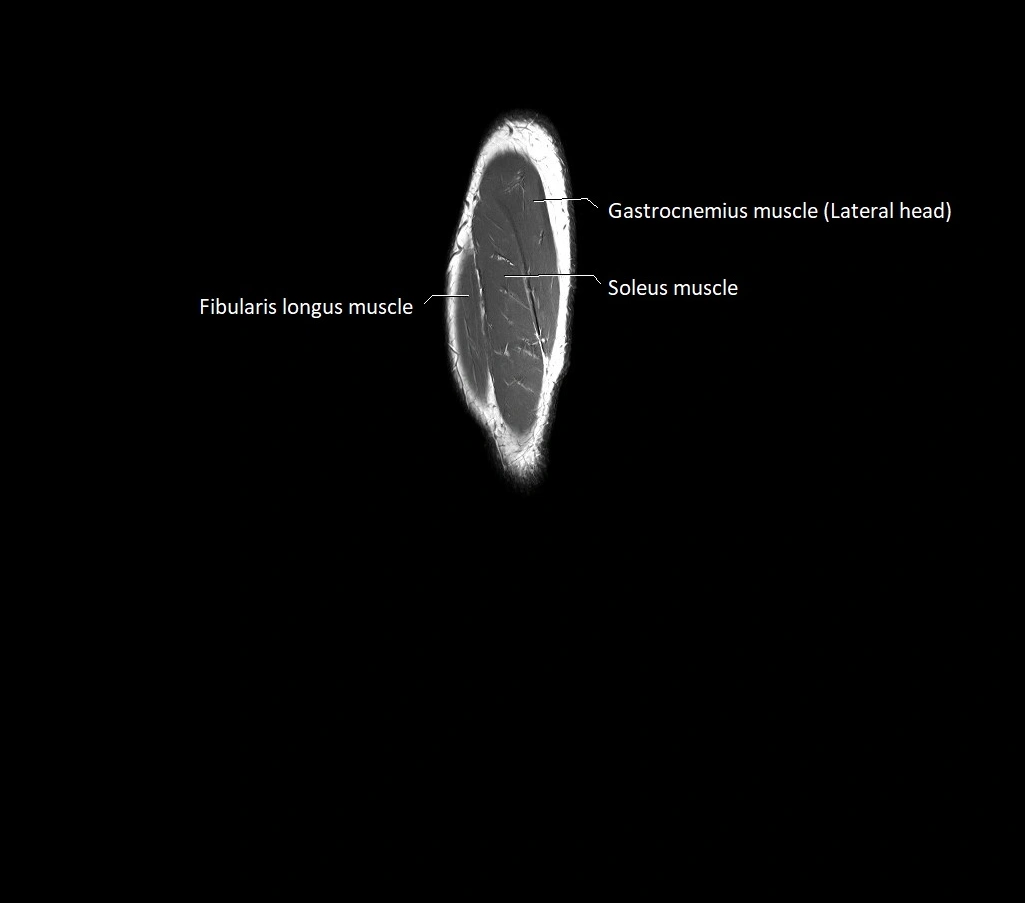

MRI image